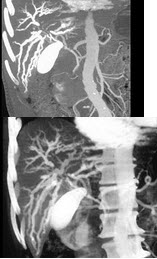

男,58岁,有高血压病史,突发胸背剧痛,CT扫描如图,其最可能的诊断为( )

A:主动脉瘤

B:主动脉假性动脉瘤

C:主动脉窦瘤破裂

D:高安病

E:主动脉夹层动脉瘤